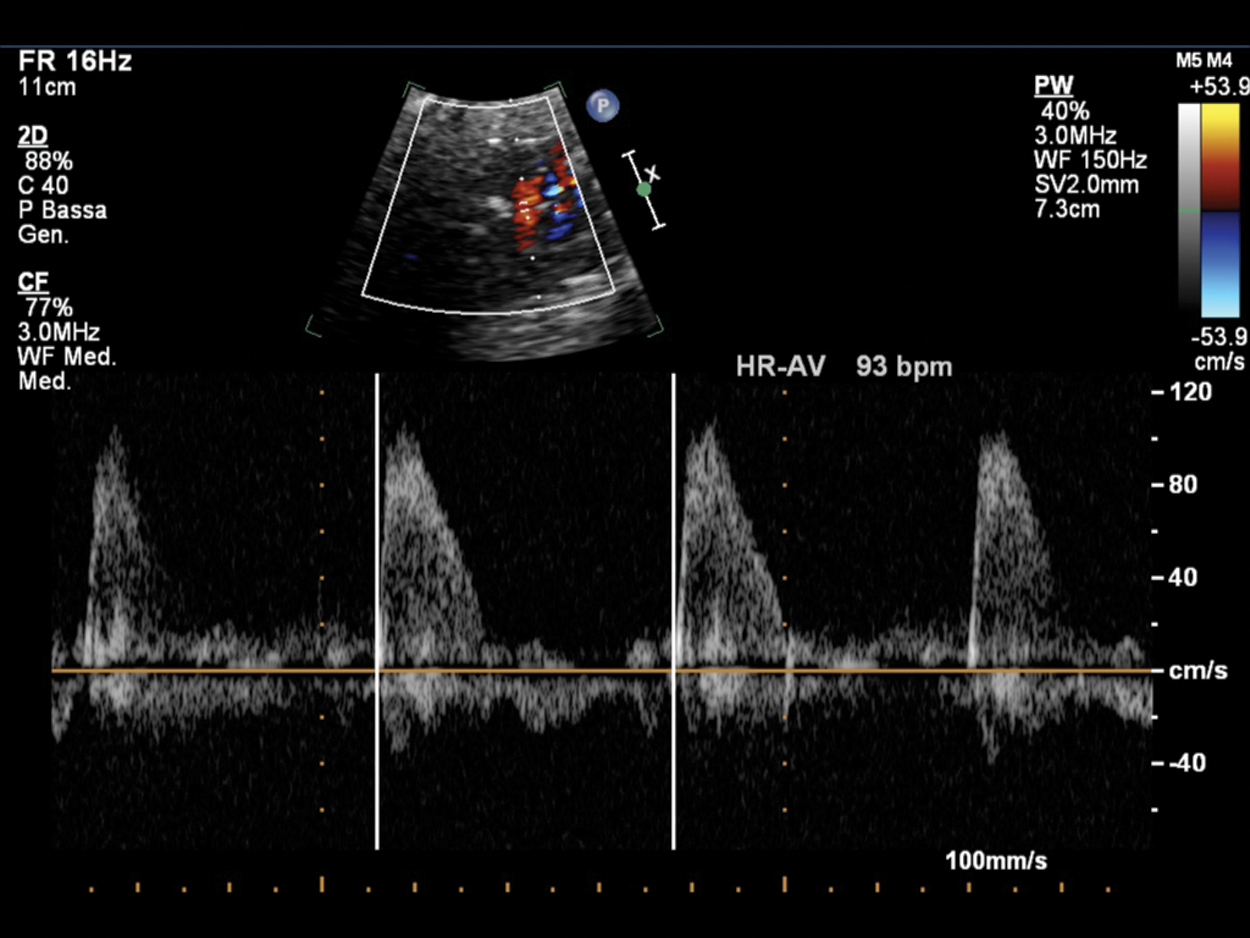

Figure 12: Fetal bradycardia (FHR 93 bpm) in a pregnant at 35 GA probably due to LQTS; the suspicion is related to the family history of a previous son who died at 2 months of life for LQTS and noncompaction myocardium. PW Doppler cursor placed through aortic valve. HR-AV: Heart rate—aortic valve

Sinus bradycardia shows regular intervals between ventricular contractions (V-V interval) measured by M-mode or Doppler recordings through which accurate assessment of the pattern of atrial activity (regular or irregular A-A interval) and the temporal relationship between each atrial and ventricular activity (AV interval) can be performed. This analysis is defined as “the cornerstone” that allows correct diagnosis of any form of arrhythmia’s underlying electrophysiological mechanism. When the A-A intervals have little different lengths (Fig. 11), it needs to measure the A-A intervals over a period of time and the AV interval for each cardiac cycle. Five to 10 cardiac cycles are usually sufficient to evaluate the electrophysiological mechanism, but it is recommended to repeat various assessments to confirm diagnosis [2].

Pulsed Doppler (Figs. 4–12) recordings of simultaneous left ventricular inflow and outflow, superior vena cava and ascending aortic flow, or pulmonary artery and pulmonary venous flow permit documentation of the relationship between mechanical atrial and ventricular systole [6].